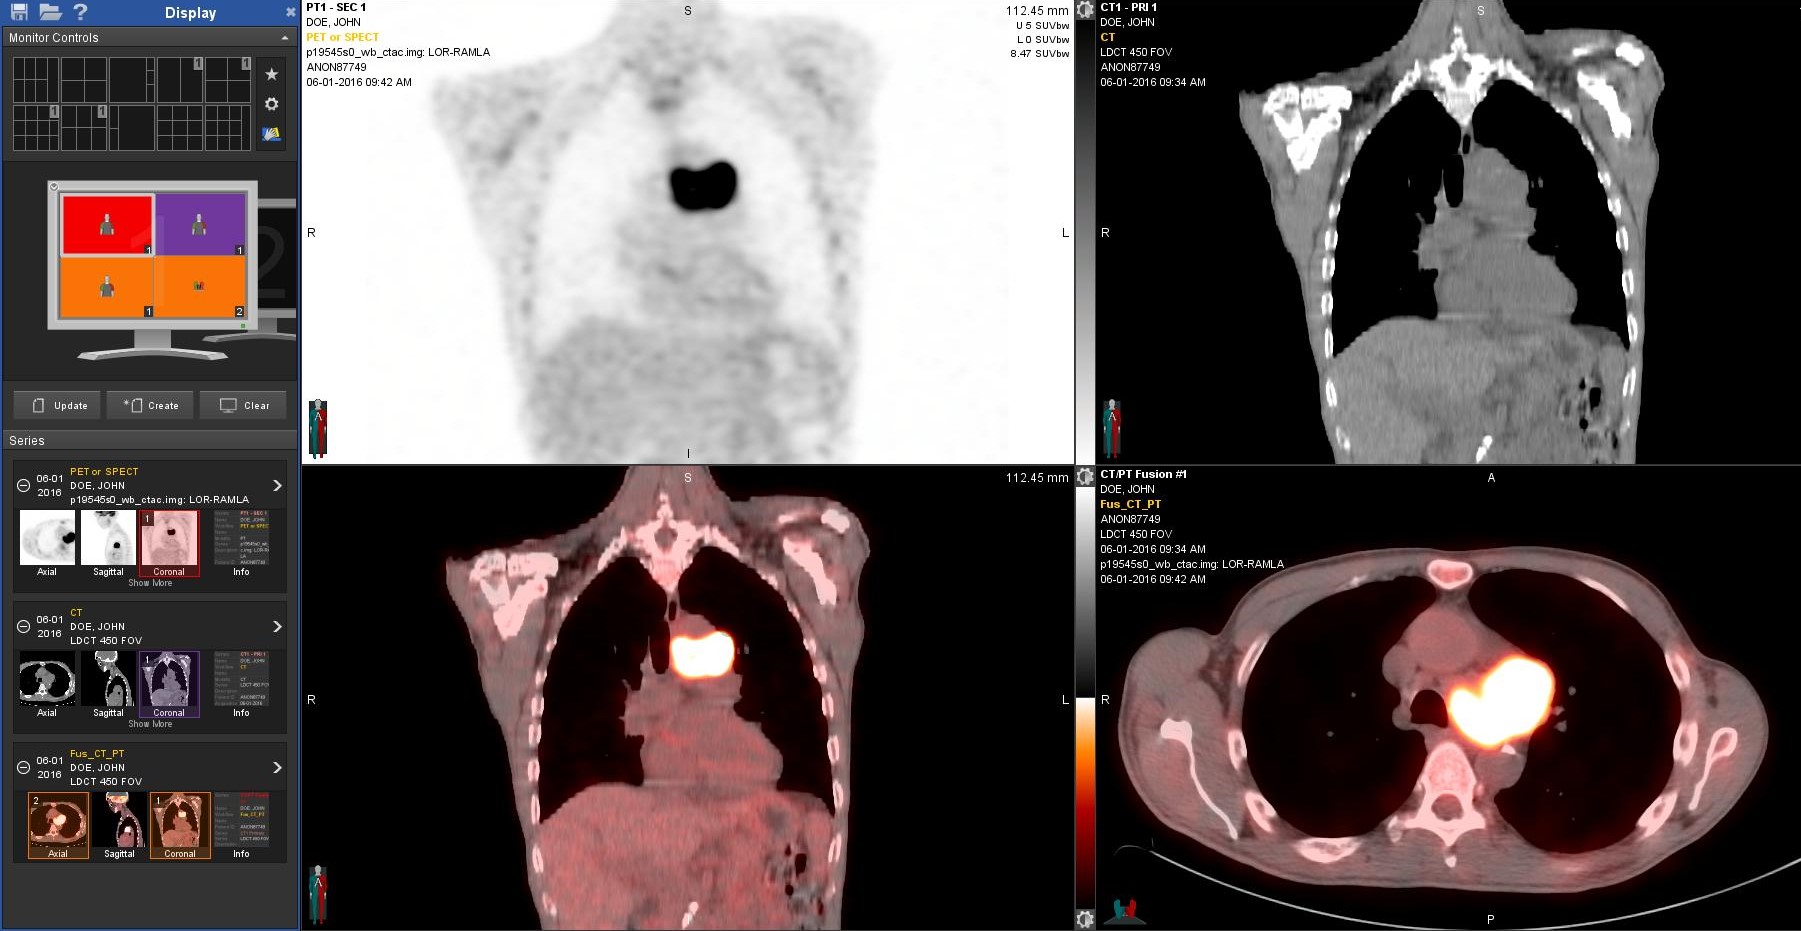

Nuclear Medicine/PET Imaging

Nuclear Medicine studies give a detailed view of what is happening in the body at a molecular or cellular level. This type of medical imaging is used to diagnose and manage the treatment of cancer, heart disease, and disorders of the lungs, bones and kidneys. Nuclear Medicine exams use a radiopharmaceutical (a substance that emits a small amount of x-rays from within the body). The x-rays, or gamma rays, are measured with special detectors.

PRI radiologists are among the most experienced in the Greater Cincinnati area in interpreting PET scans and correlating PET with other imaging modalities, such as CT and MRI. PRI radiologists were the first to begin interpreting PET scans in the city of Cincinnati. The PRI radiologists who interpret PET imaging have developed excellence in interpreting a high volume of PET imaging used in the initial diagnosis, staging and subsequent re-staging of many different kinds of malignancies, such as lymphoma and myeloma and cancers of the lung, breast, prostate, reproductive tract, pancreas, head and neck, and skin. Our radiologists work closely with the referring physicians to aid the referring physician in determining the appropriate course of action or therapy for their patients.

PET/CT scan showing hypermetabolic tumor within the chest.